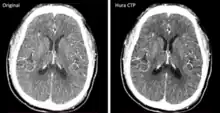

Photon-counting CT detectors (2022)

The development and FDA clearance of photon-counting detectors (PCD) for computed tomography (CT) scans in 2022 was an important innovation. These detectors offer a more efficient process for converting X-rays to electrical signals, allowing for better material differentiation and potentially reducing the radiation dose for patients. The image to the right shows two scans of the same brain using old and new CT technology respectively.[24]